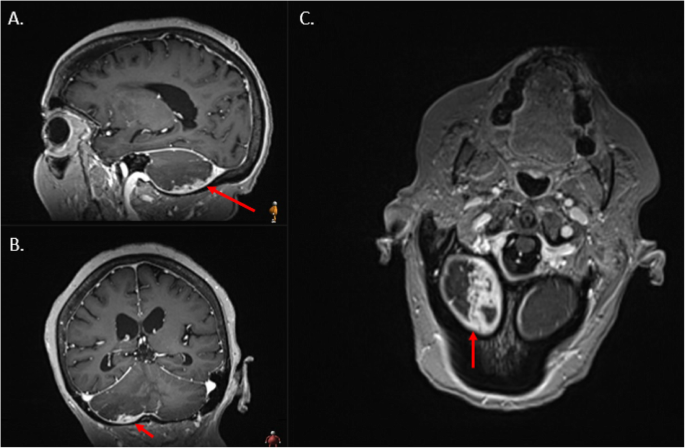

A 77-year-old female with a history of chronic kidney disease and type II diabetes mellitus underwent workup for ongoing sinusitis, fatigue, malaise, and 20-pound weight loss. Patient quit smoking 30 years ago and denies any drug or alcohol use. She reports no significant family history including history of malignancy. MRI of the brain performed at an outside hospital to evaluate the extent of sinusitis revealed a posterior fossa lesion with surrounding edema causing compression on the fourth ventricle. The patient was transferred to our institution for neurosurgical evaluation. On presentation the patient was found to have mild cerebellar signs but an otherwise non-focal exam. Patient was surprised to learn of the cerebellar findings considering her lack of significant symptoms. MRI of the brain, including 3DT1, and T2 Flair showed an irregular enhancing lesion along the inferior & posterior surface of the right cerebellar hemisphere suggestive of an infiltrative malignancy (Figs. 1 and 2). Based on these imaging findings, top differentials at the time included a metastatic disease process, an atypical meningioma, or a glioma. Upon retrospective review of this case and imaging findings, an additional differential was hypertrophic pachymeningitis. Contrast CT of the chest, abdomen, and pelvis was then performed and found to be negative for a primary malignancy. H1-MR-spectroscoy was not considered prior to resection. After discussion with the patient and her family, she elected to undergo open biopsy with or without further resection of the lesion. One week after her initial referral, she was taken to the operative theater and underwent a suboccipital craniotomy.

Axial T2 FLAIR sequence MRI at the level of the 4th ventricle within the posterior fossa demonstrating diffuse right cerebellar hyperintensity (long red arrow) and to a lesser extent left cerebellar hemisphere hyperintensity (short red arrow) corresponding to the large amount of vasogenic edema produced by the lesion